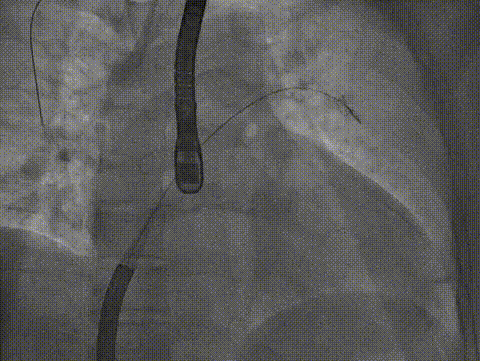

术中影像

房间隔穿刺

导引鞘置入左房

房间隔穿刺高度

导引鞘置入